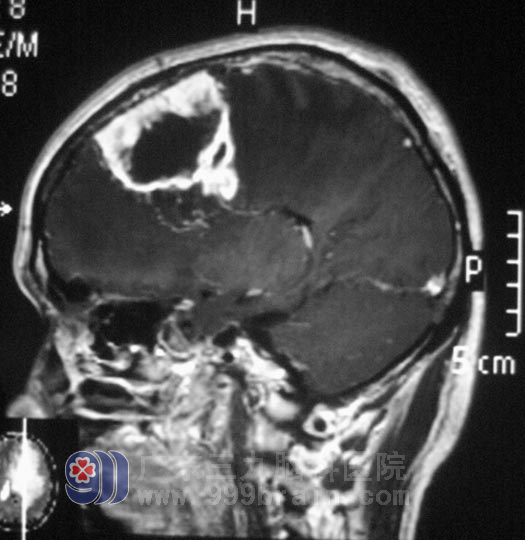

王先生,年过半百,一年前无明显诱因开始出现头痛、头晕,在当地医院对症治疗,症状反复。三天前头痛、头晕症状较前加重,伴恶心、呕吐胃内容物,精神状态差,家人送当地市医院就诊,行头颅检查结果提示:左额叶占位,直径约4cm。

在广东三九脑科医院综合神经外科完善相关检查后,由鲁明主任主刀,在全麻下行“左额镰窦旁肿瘤切除术+去骨瓣减压术”,术中板障出血凶猛,显微镜下见灰白色肿瘤组织,肿瘤表面血管丰富,畸形明显,杂乱生长,肿瘤与大脑镰粘连紧密,并侵犯上矢状窦,脑组织肿胀明显,予行去骨瓣减压。手术顺利结束。术后头颅MR复查未见明显肿瘤残留。